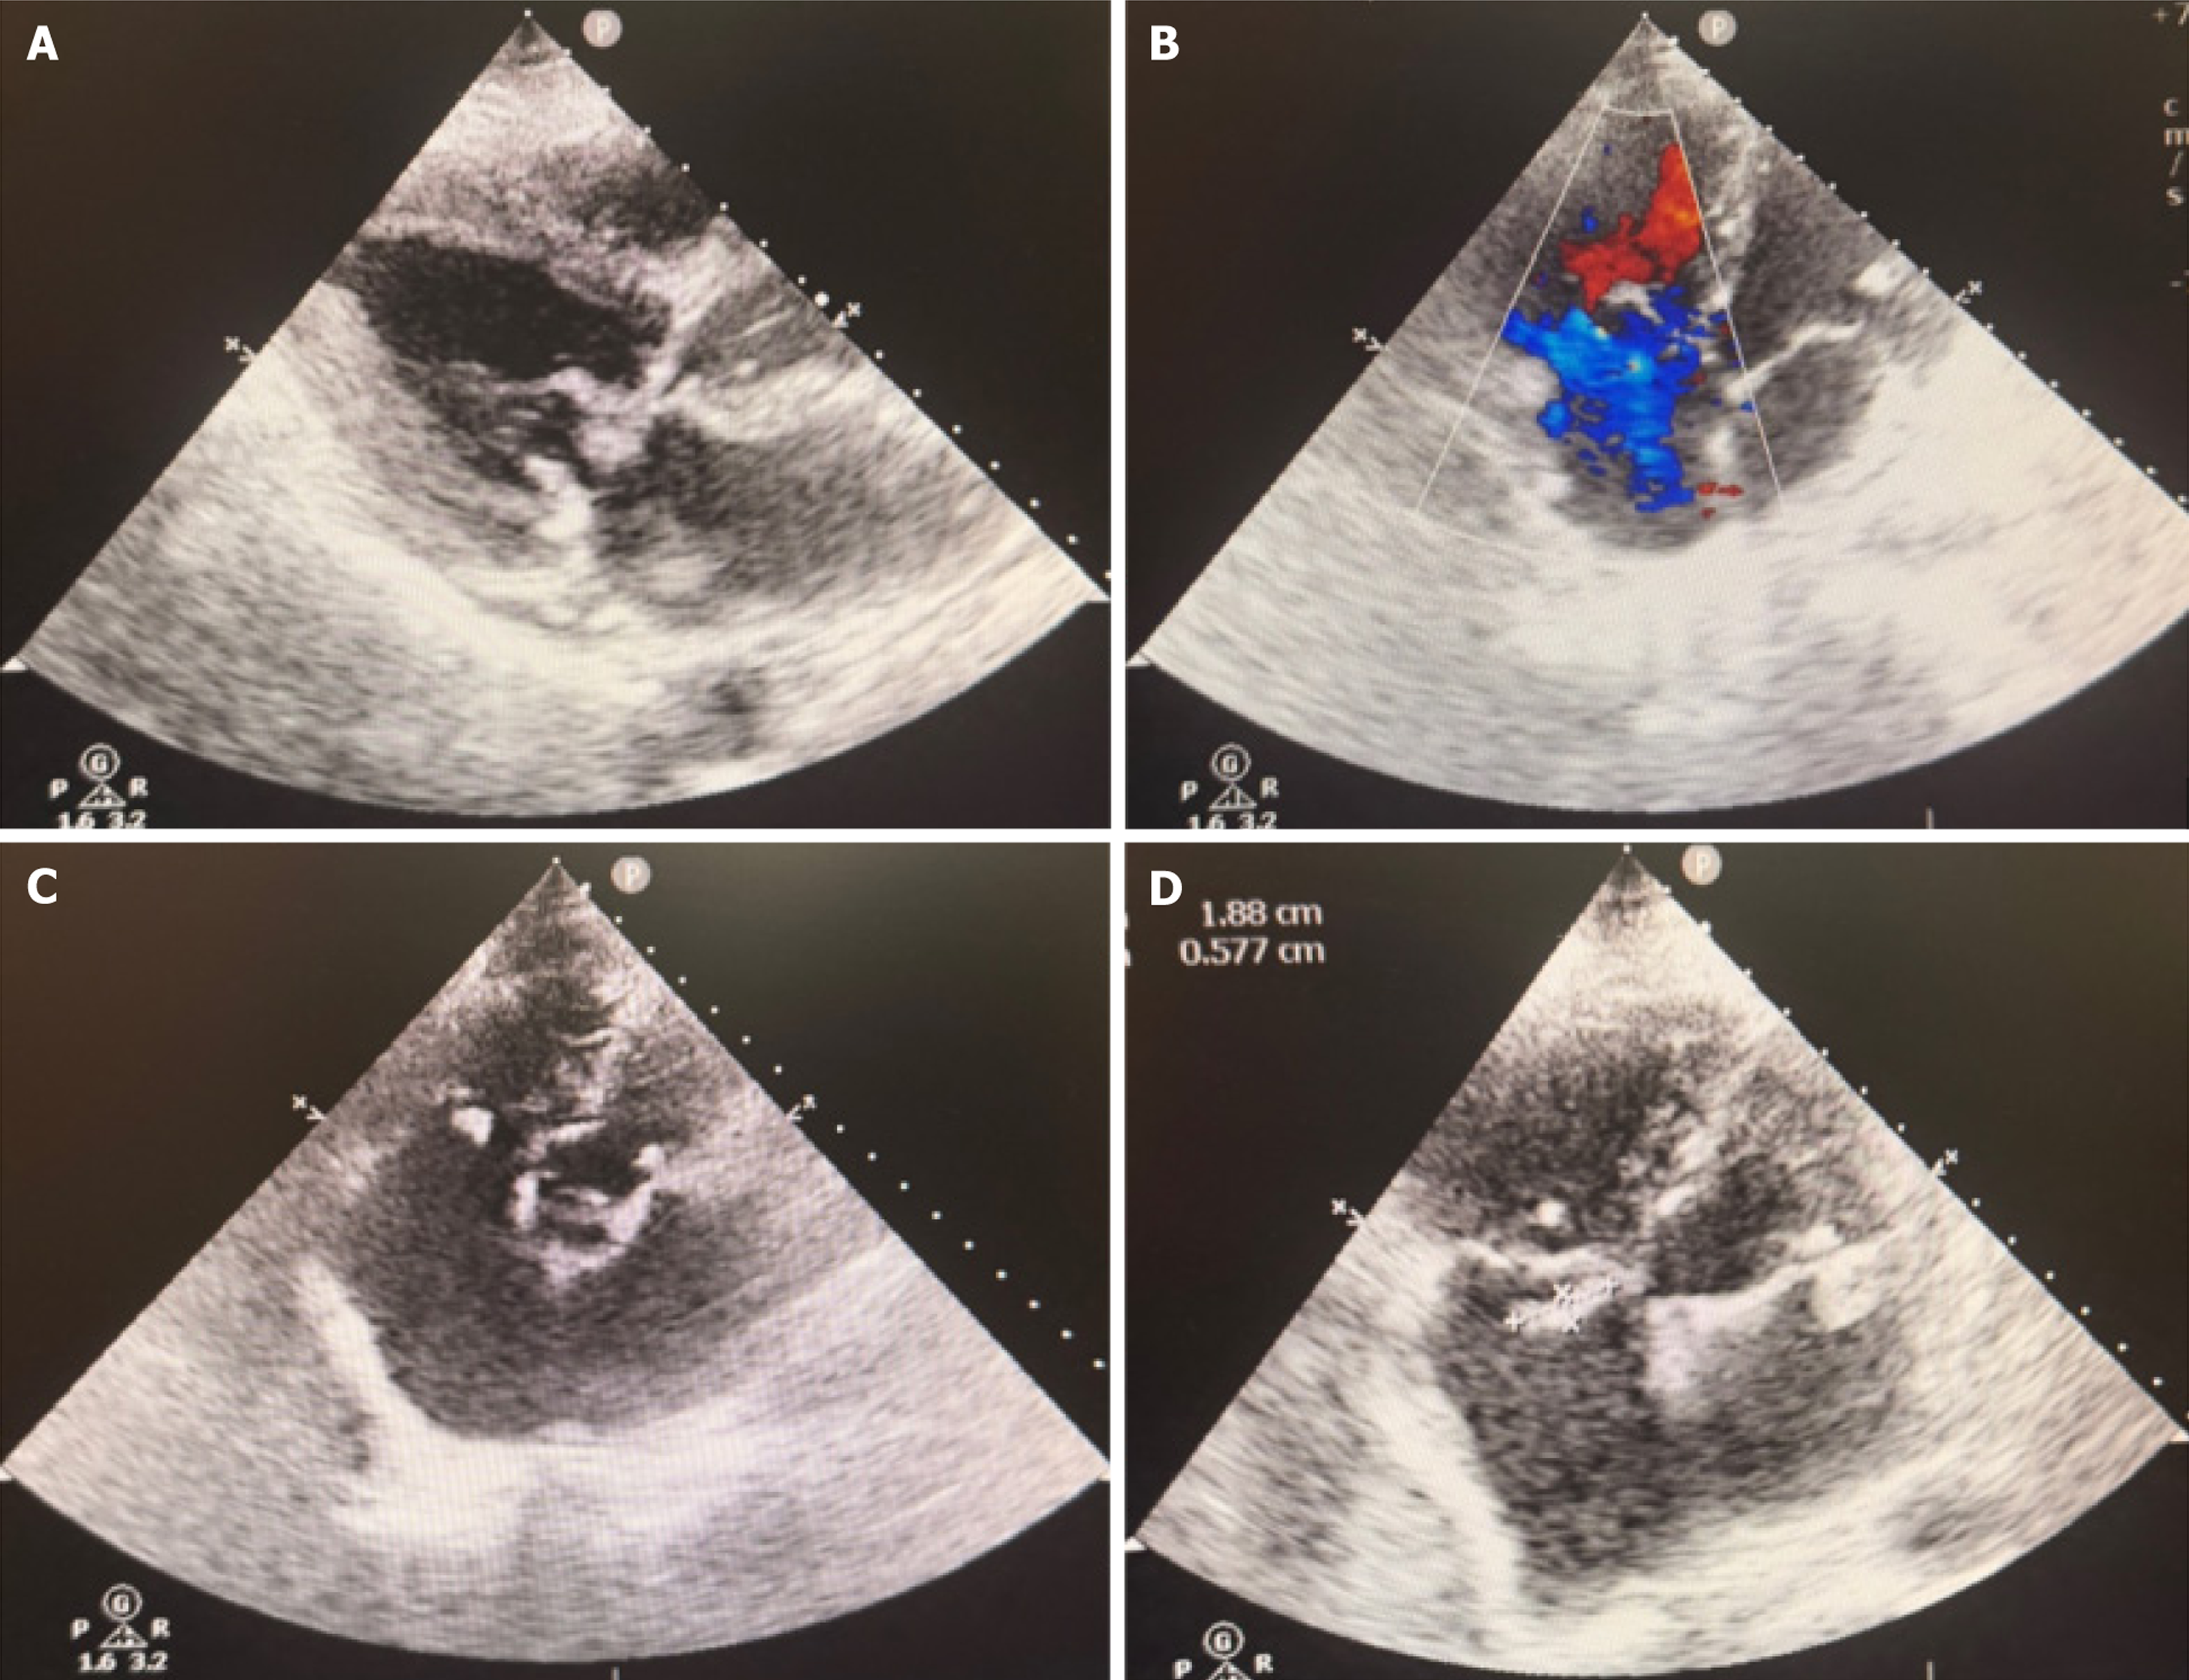

Figure 1 Composite transthoracic echocardiographic images demonstrating multivalvular vegetations and regurgitation.

A and B: Large mobile vegetations on the anterior mitral leaflet with colour Doppler flow indicating moderate mitral regurgitation; C and D: Vegetations involving the tricuspid valve, with concomitant mitral valve involvement.